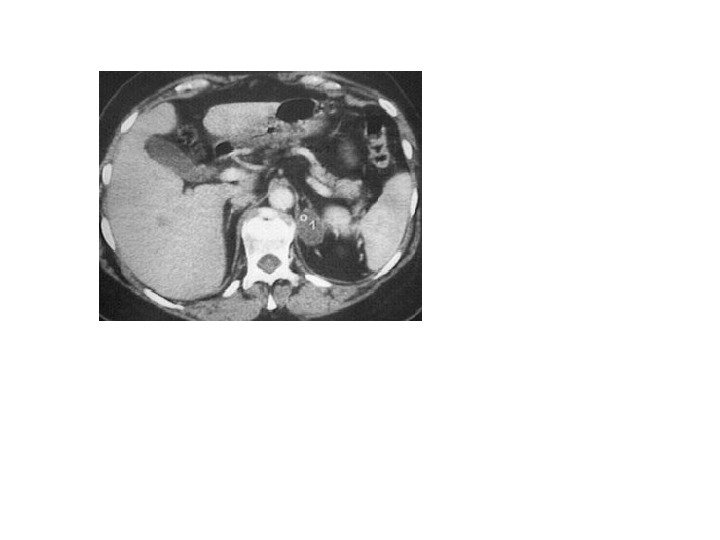

• В 10% случаев при феохромоцитоме компьютерная томография выявляет двустороннее поражение надпочечников. • Билатеральная феохромоцитома часто проявляется как незначительное увеличение надпочечников, с заметным повышением их васкуляризации. • Необходимо помнить, что феохромоцитома может иметь и вненадпочечниковую локализацию, располагаясь в паракавальных симпатических ганглиях, симпатических ганглиях средостения, ганглиях стенки мочевого пузыря.

• В 10% случаев при феохромоцитоме компьютерная томография выявляет двустороннее поражение надпочечников. • Билатеральная феохромоцитома часто проявляется как незначительное увеличение надпочечников, с заметным повышением их васкуляризации. • Необходимо помнить, что феохромоцитома может иметь и вненадпочечниковую локализацию, располагаясь в паракавальных симпатических ганглиях, симпатических ганглиях средостения, ганглиях стенки мочевого пузыря.